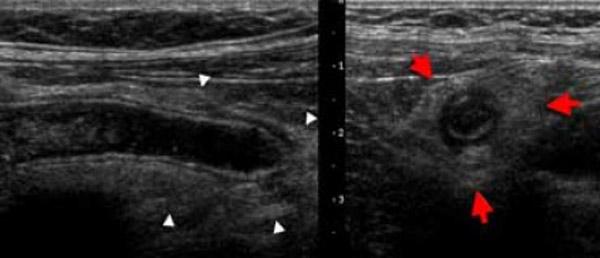

Mirizzi SYndrome

impacted stone in the cystic duct or GB neck

presence of two tubular structures representing the bile duct above the level of the cystic duct

Mirizzi SYndrome

impacted stone in the cystic duct or GB neck

presence of two tubular structures representing the bile duct above the level of the cystic duct